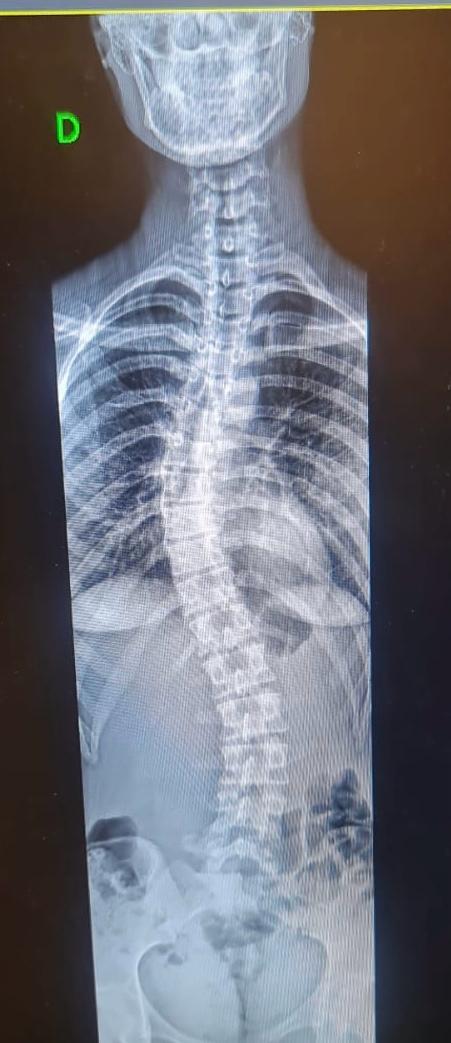

O Hospital Ortopédico do Estado da Bahia, que é gerido pelo Einstein e possui atendimento 100% público, oferece de forma inédita aos pacientes do SUS no estado o exame de escanometria. O procedimento, uma espécie de Rx digitalizado, antes disponível na Bahia apenas na rede privada de saúde, realiza medidas do corpo e dos membros do paciente, permitindo avaliar com precisão o crescimento e o desenvolvimento dos ossos, assim como os desvios da coluna vertebral, que acometem faixas específicas da população.

A escanometria ajuda a identificar diversos problemas com antecedência, entre eles deformidades e lesões traumáticas, além de contribuir na preparação e acompanhamento de tratamentos cirúrgicos e clínicos envolvendo ossos e articulações. “O exame auxilia a equipe médica a entender melhor as necessidades específicas de cada paciente, contribuindo para um diagnóstico mais preciso e um plano de tratamento mais adequado, como o uso de órteses, por exemplo”, explica Niklas Söderberg, gerente médico do Hospital Ortopédico do Estado da Bahia.

O exame é ideal para verificar alterações estruturais nos membros, coluna e até no alinhamento das pernas e dos braços. O procedimento passou a fazer parte do moderno centro de bioimagem do hospital, ampliando sua capacidade de atendimento. Na unidade, já foram realizados 329 escanometria, nos quais foram possíveis observar de forma detalhada toda a estrutura óssea dos pacientes, por meio de sensores extremamente precisos, facilitando e acelerando o diagnóstico médico.